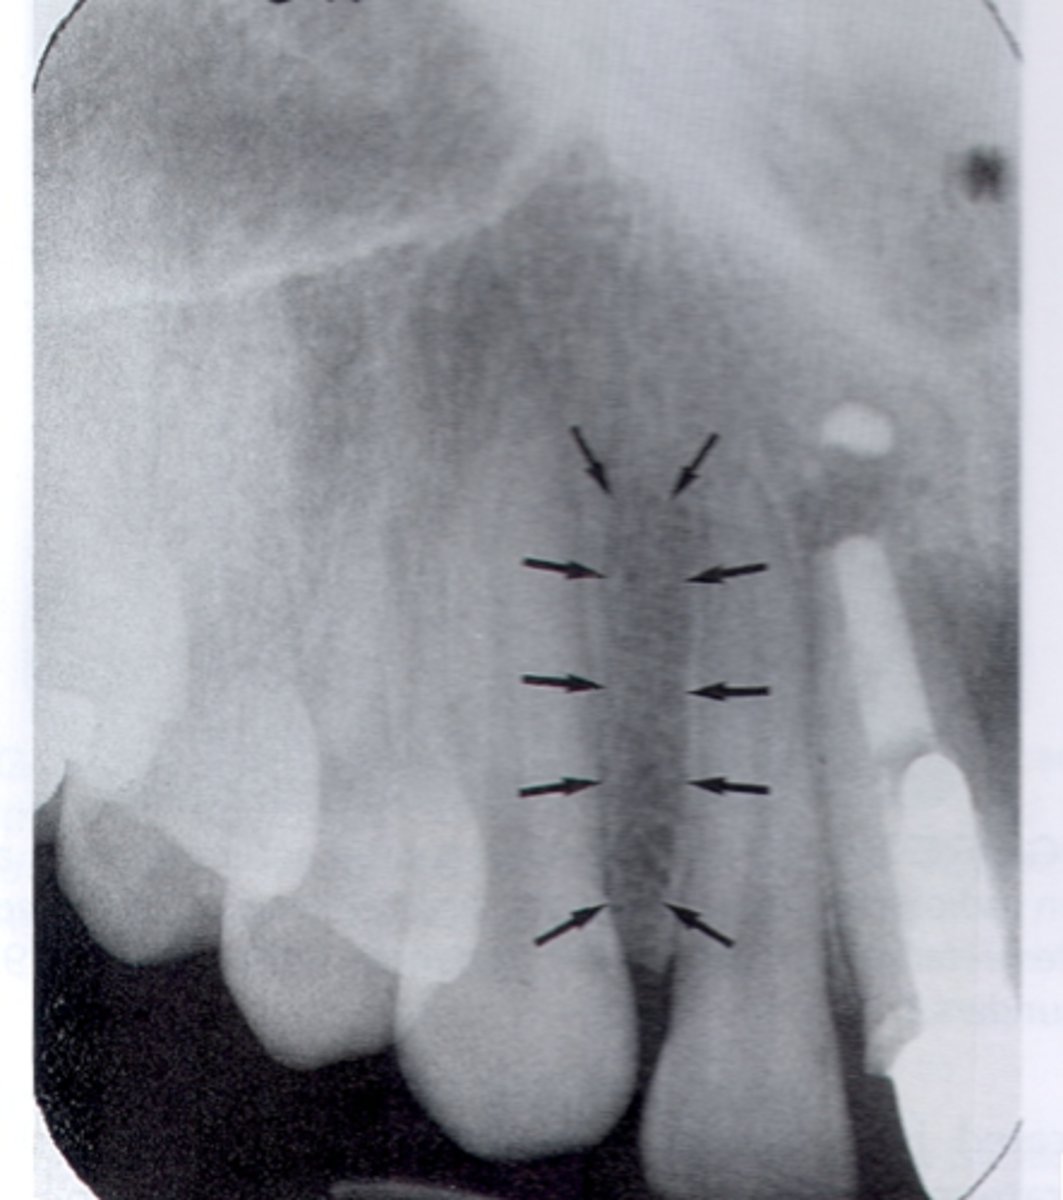

Periodontal ligament space

What is the radiolucent structure seen here?